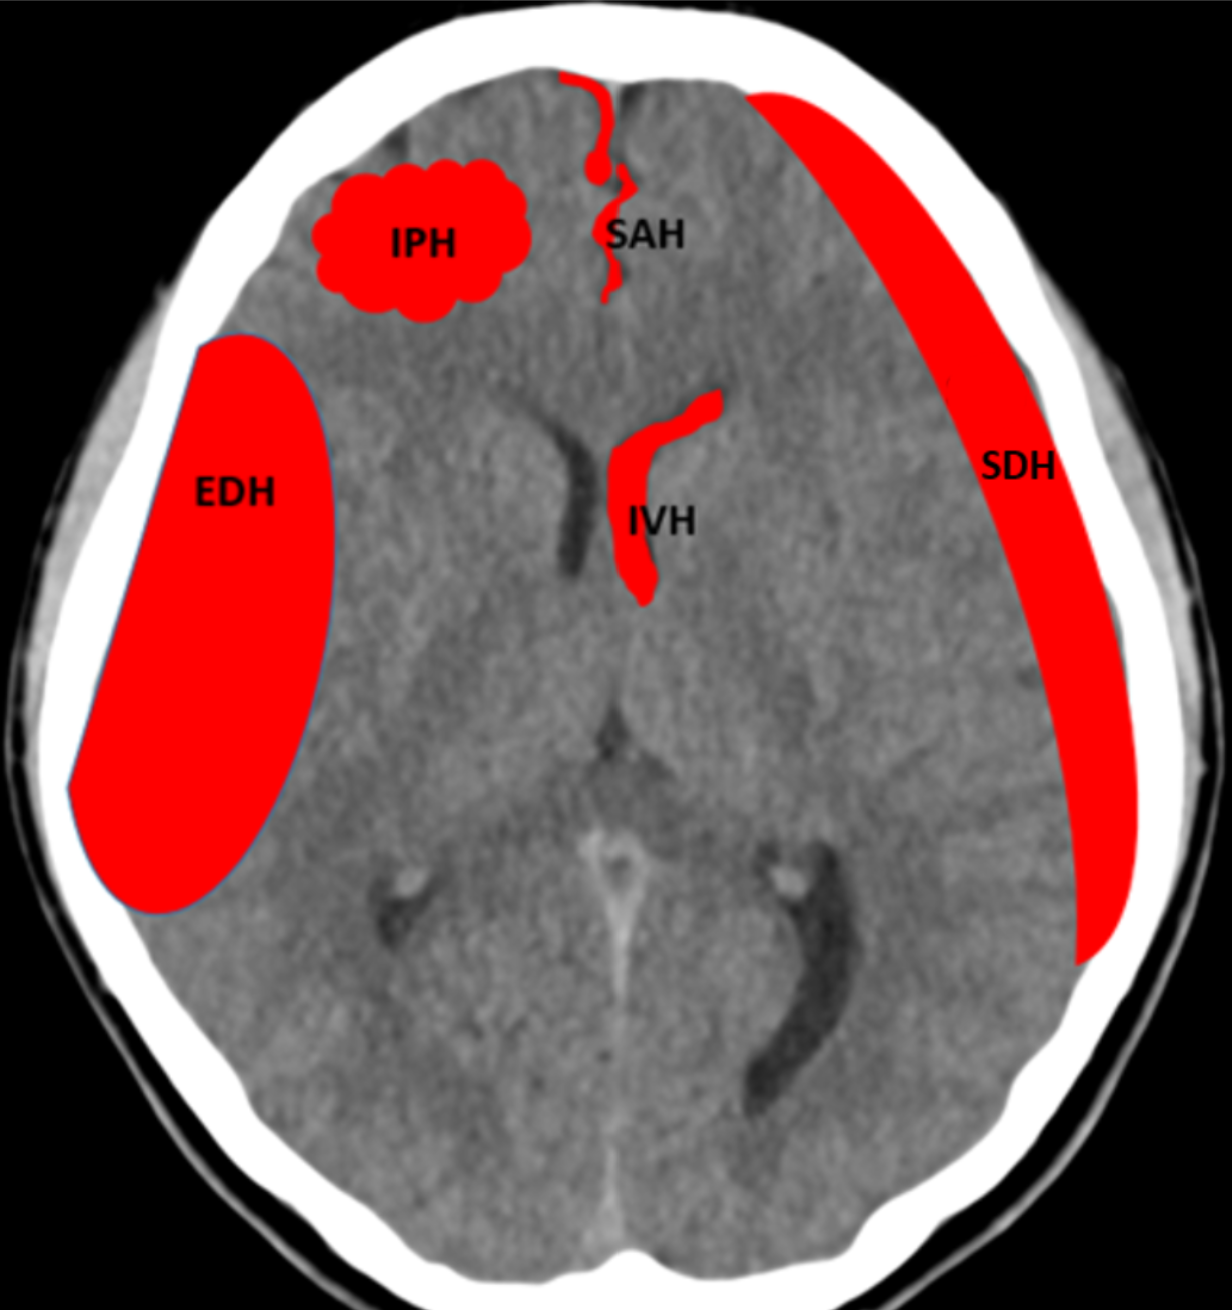

Demographic data were retrieved, including the time when: 1) CT was performed, and 2) the radiologist signed the report. Two patient groups were created based on whether an ICH was detected or not. Within the ICH detected group the clinician further classified the bleed etiology as being: epidural hematoma (EDH), acute subdural hematoma (ASDH), subarachnoid hemorrhage (SAH), intraparenchymal hematoma (IPH), or intraventricular hematoma (IVH), as well as evidence of mass effect (Figure 1-b). As this was a live consecutive patient population other pathologies were also encountered and were classified as non-ICH with other pathologies i.e., tumor, non-hemorrhagic stroke, etc. All information was retrieved from PACS and the signed radiology report (Figure 1-c).